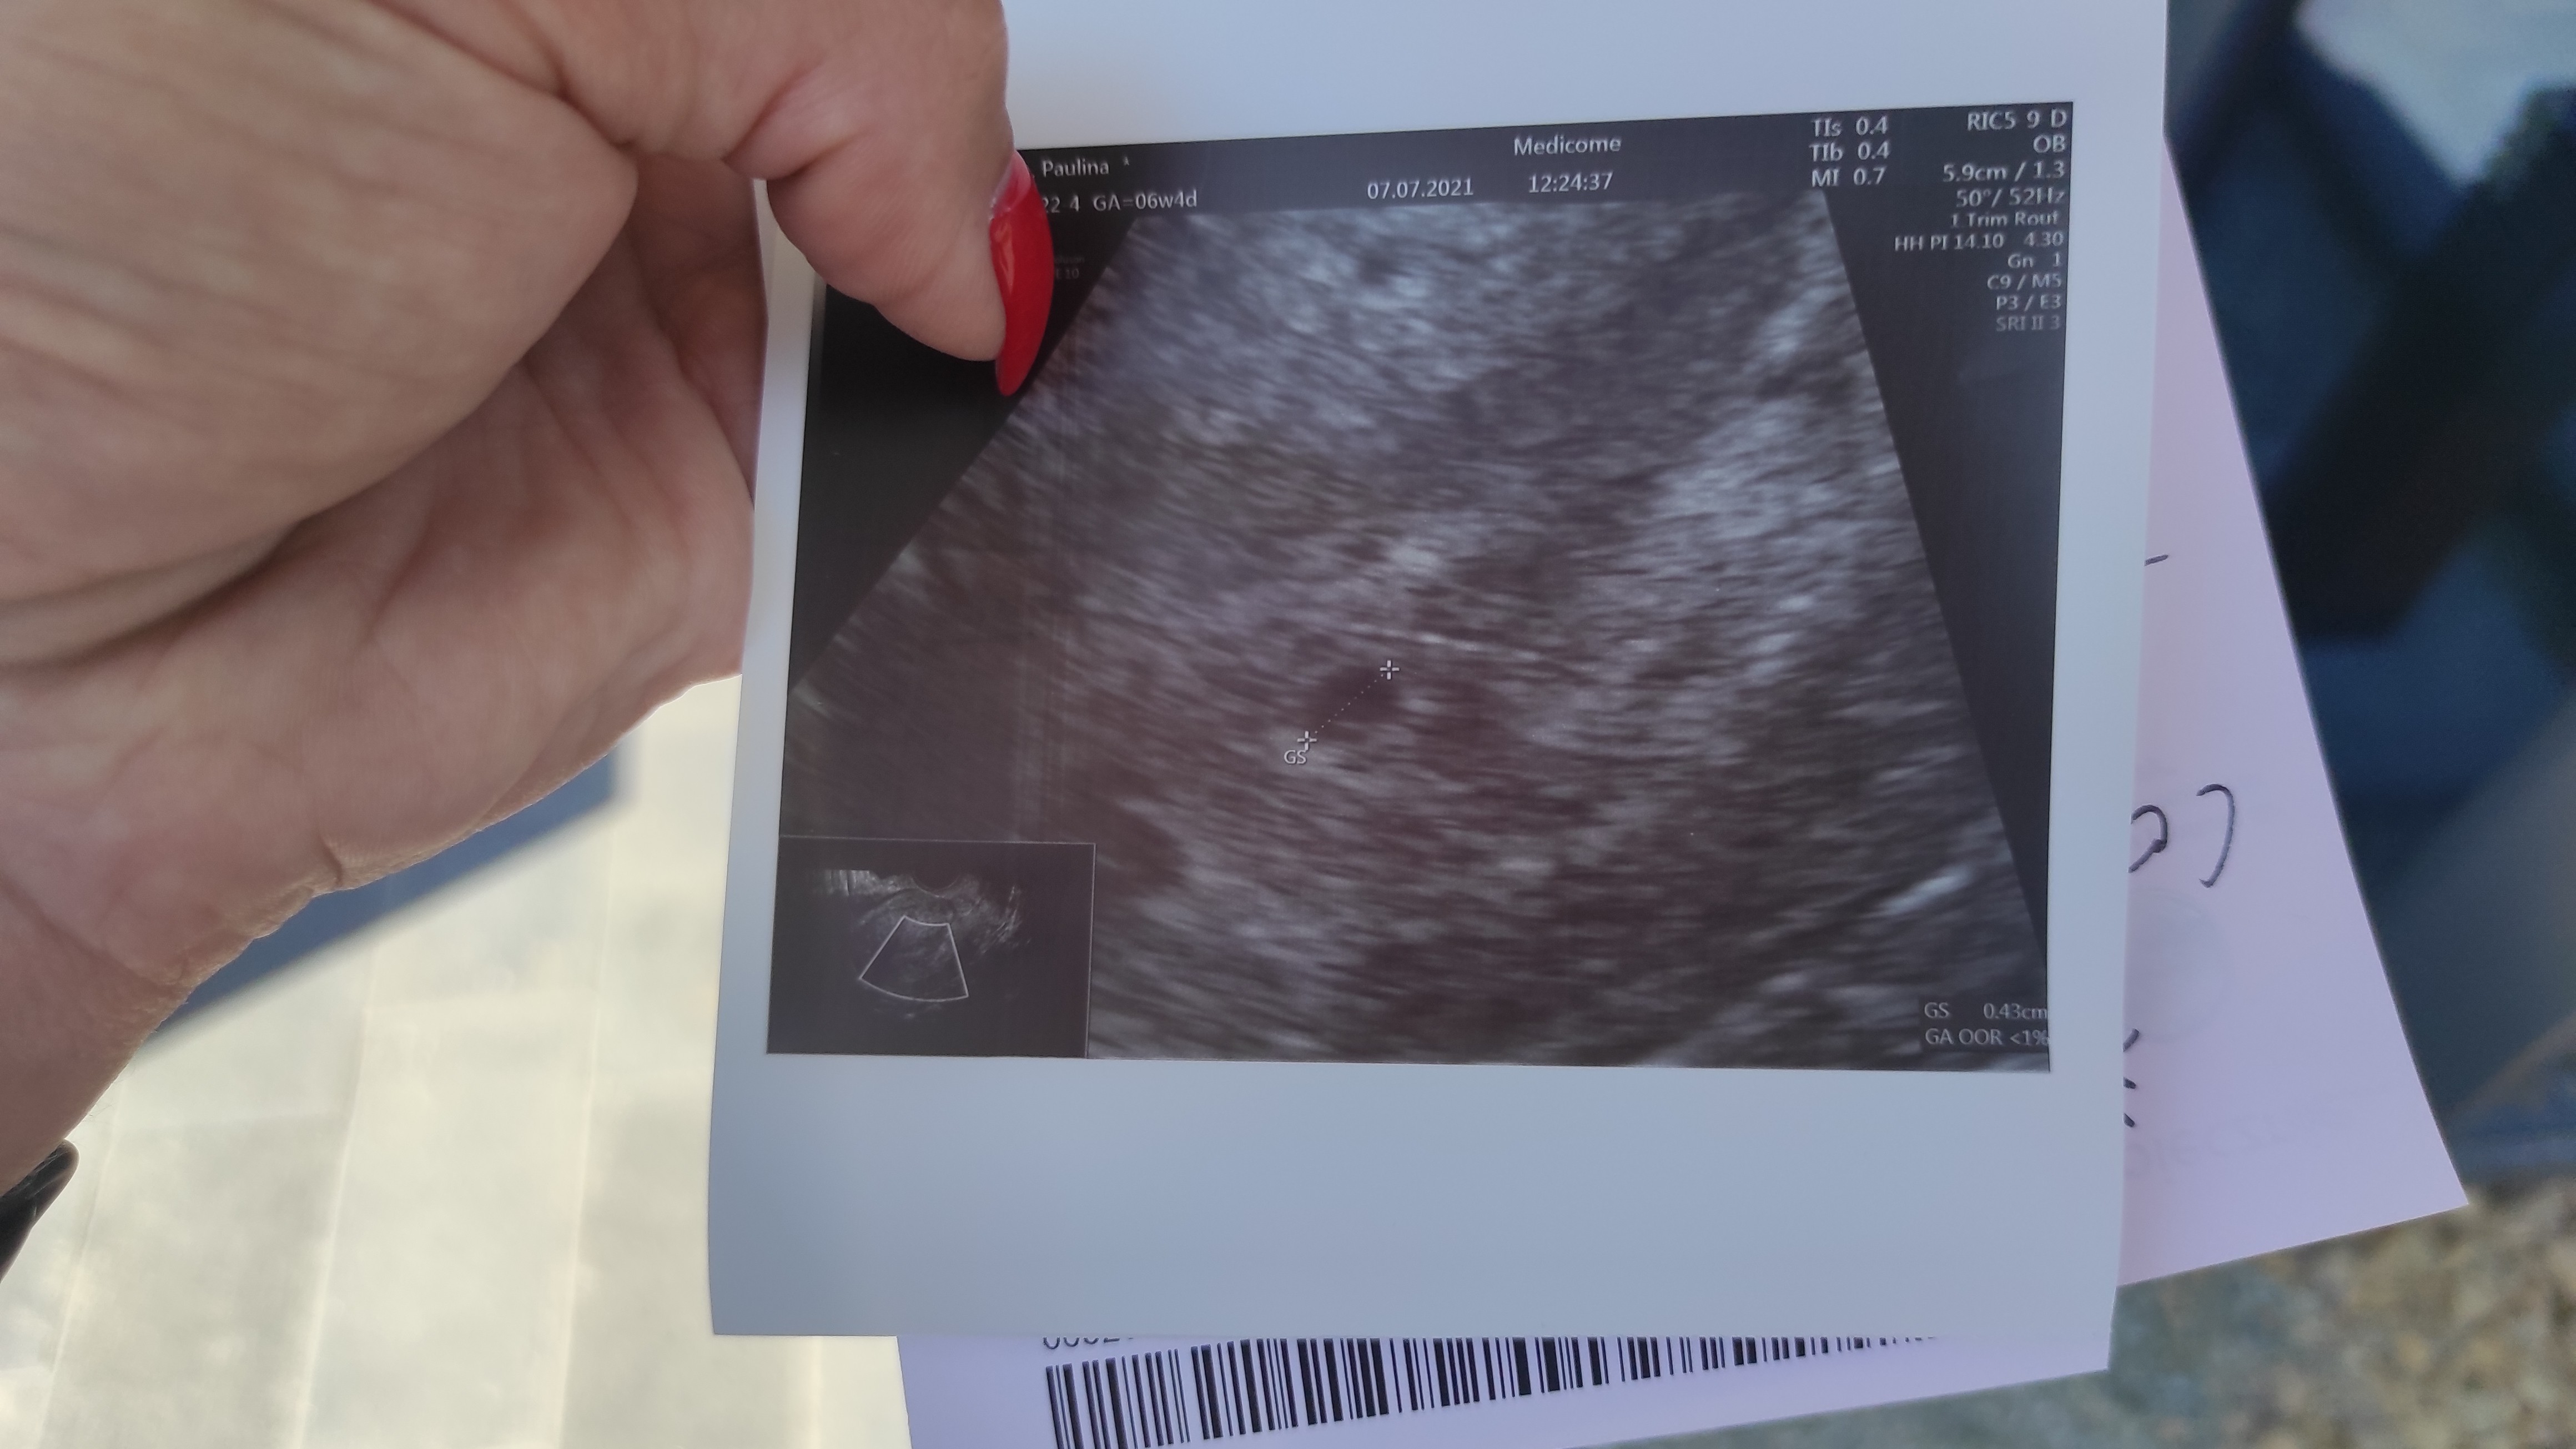

) i pomimo, że się oczyscilam w 8 tyg. to długo utrzymywała się beta mimo, że to było tylko puste jajo płodowe bez zarodka ;(